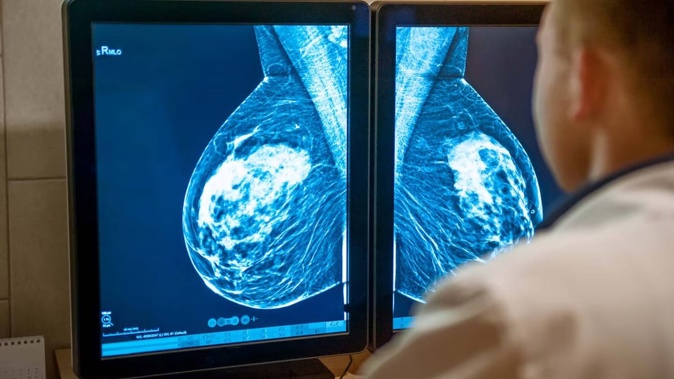

An official inquiry has found breast cancer screening delays of up to nine months in the Wellington region may have harmed 10 women.

It shows almost two-thirds of women, or 8100, enrolled by Breast Screen Central from 2017-2021 waited longer than the target of 60 days to be seen.

The expert review team concluded that for 10 women, “earlier screening may have resulted in their cancer being at a less advanced stage at the time of diagnosis or requiring less intensive treatment”.

Their 25-page report said “harm could not be defined but that these individuals had not received the full benefit of the screening programme”.

Of those 8100, 59 were eventually diagnosed with breast cancer, and the reviewers narrowed down those with more advanced cancer to 25.

For 15 of those, the delay was “unlikely” to have made a difference, leaving 10 cases they looked at more closely, the report shows.